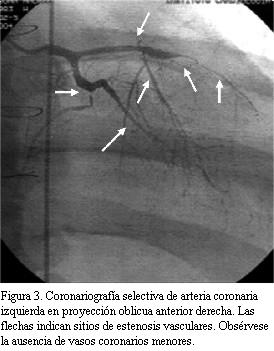

Se reitera CACG encontrándose ventrículo izquierdo severamente dilatado; hipoquinesia severa global y aquinesia apical. Insuficiencia mitral moderada.

Tronco: fino, sin lesiones. Arteria descendente anterior: se ocluye inmediatamente luego del stent en unión de tercio medio y proximal. Lecho distal se llena tenuemente por circulación colateral homocoronaria. Malos lechos distales. Arteria circunfleja: severamente lesionada a neto predominio del sector distal. Leve mejoría con nitroglicerina intravenosa. Malos lechos distales. Arteria coronaria derecha: dominante, presenta severa enfermedad distal (figura 3).

En suma: lesión severa de tres vasos con aspecto de EVI.